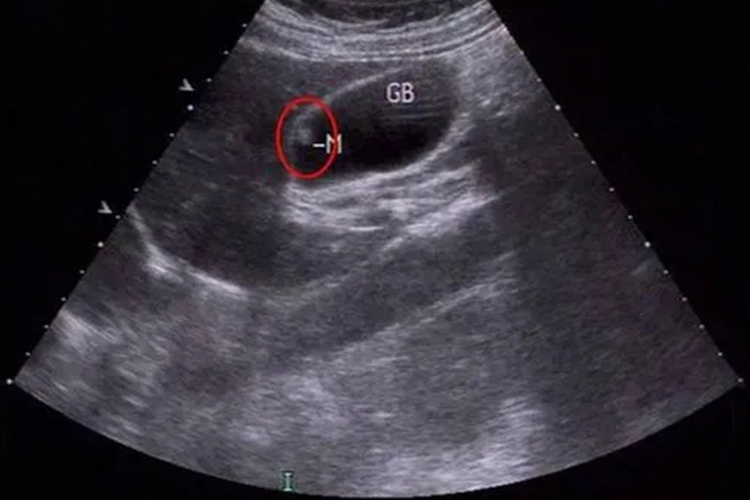

胆囊壁息肉样病变是指向胆囊腔内突出或隆起的病变,多为良性,但也有恶变的可能,包括胆固醇性息肉、炎性息肉、腺肌瘤样增生、胆囊腺瘤及恶变,应根据具体情况进行评估和治疗,定期复查,以确保及时发现和处理可能的恶变。

4、胆囊腺瘤:属于胆囊的良性肿瘤,但有一定的恶变风险。息肉通常较大,直径大于1厘米,基底较宽。患者可能无明显症状,常在体检时发现。由于其恶变潜能较高,一旦发现,多建议手术切除胆囊。

5、胆囊息肉恶变:胆囊息肉在某些因素的长期作用下,可能发生恶变,形成胆囊癌。息肉短期内迅速增大、基底部宽大、血供丰富、伴有胆囊结石等情况,提示恶变可能。此时需要尽快手术,根据病情可能需要行胆囊癌根治术,并结合放化疗等综合治疗。